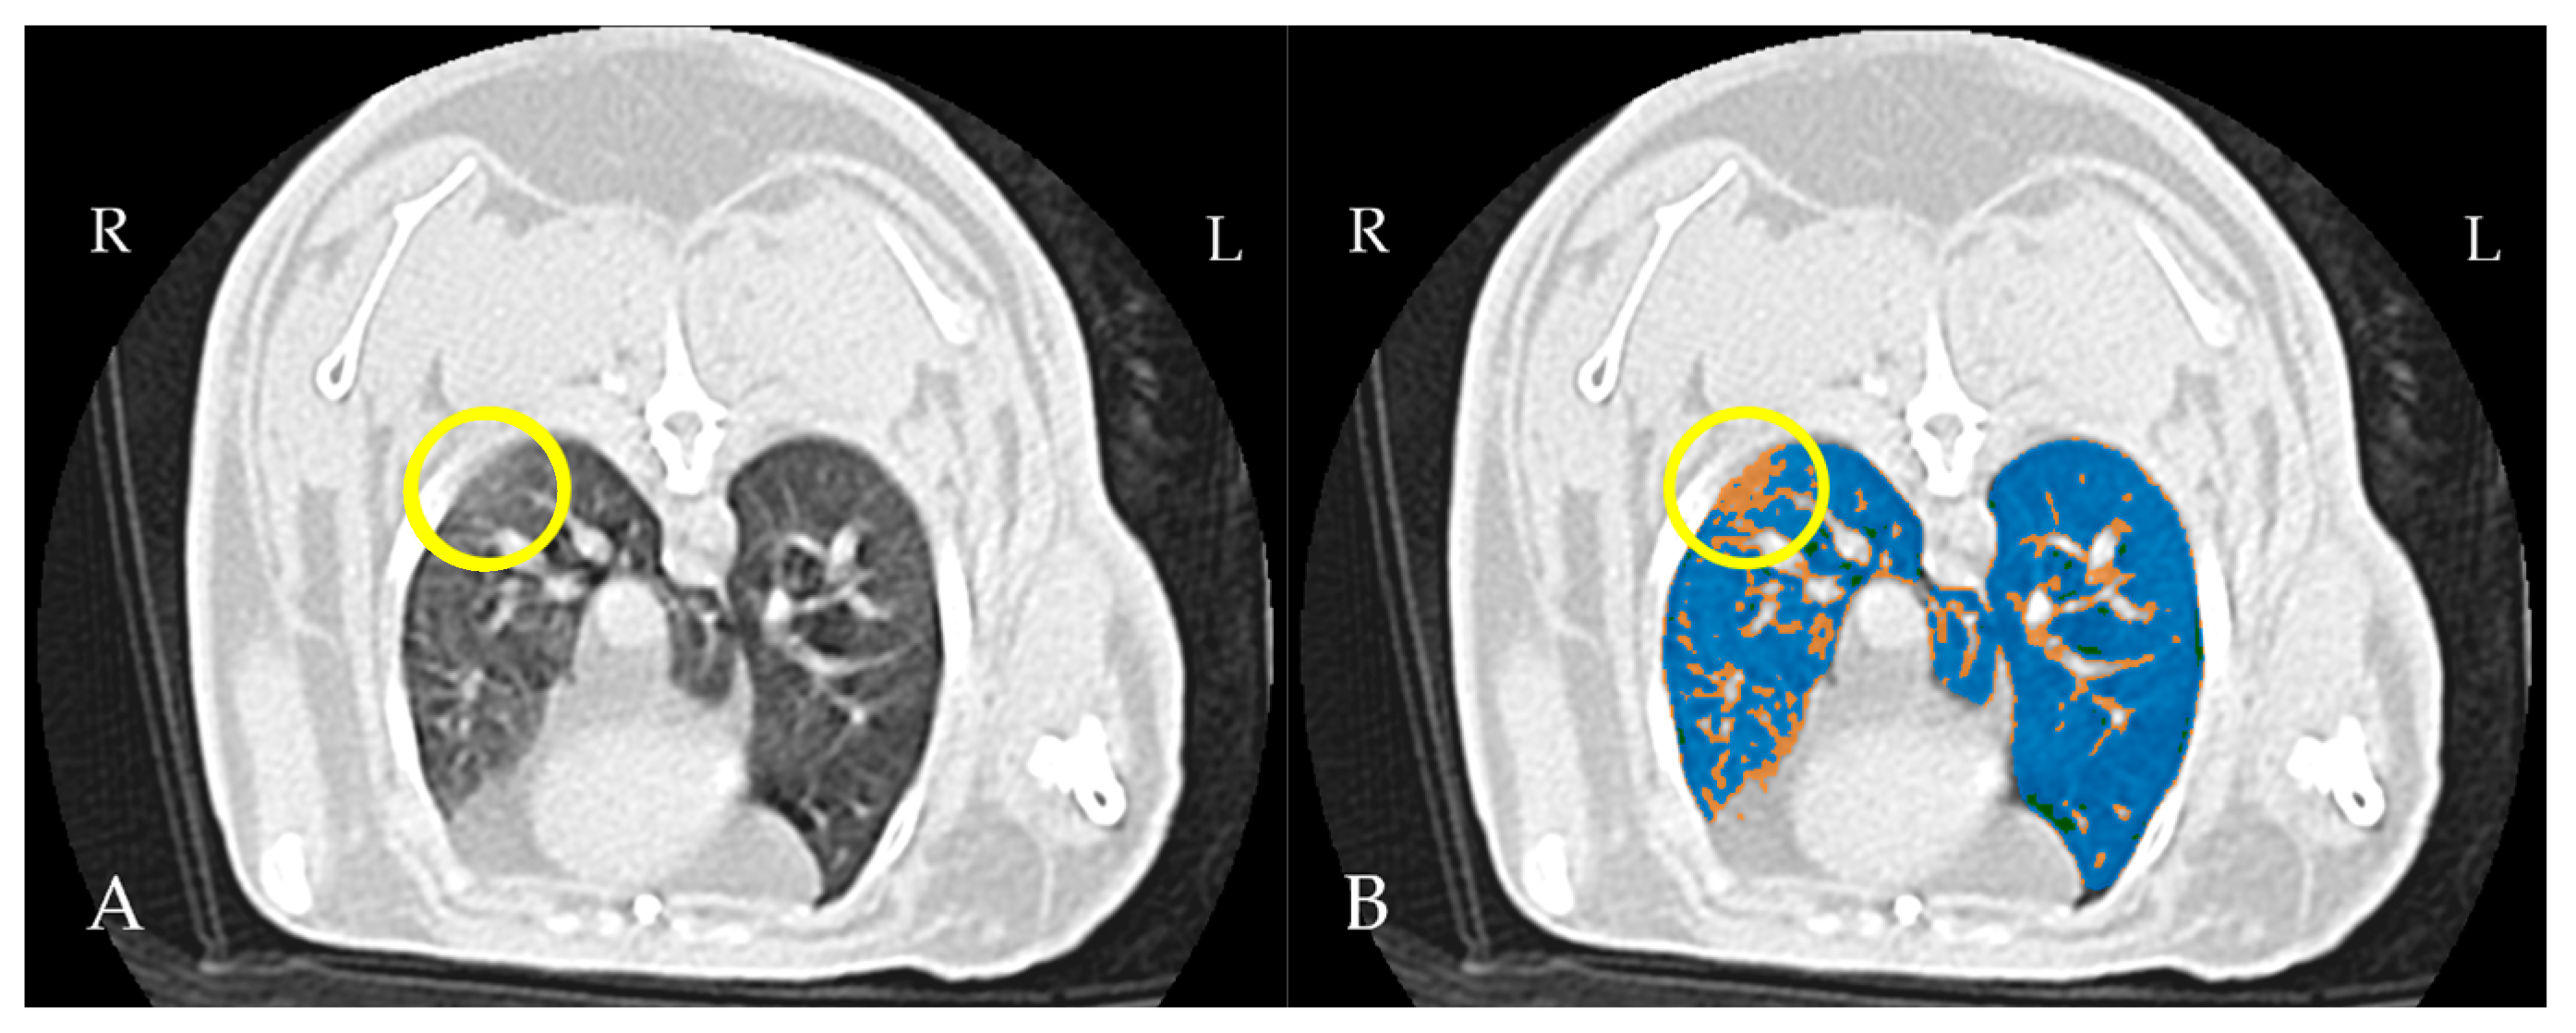

4.3. Thoracic CT